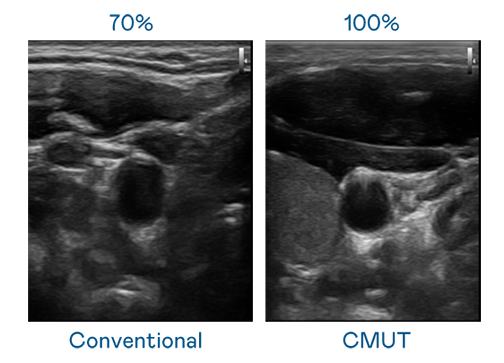

CMUT 技术是一种用电容式微机电元件来产生超音波讯号的技术。与传统 PZT 压电式技术相比,CMUT 频宽增加 30%,更宽频的超音波讯号让影像解析度大幅提升,是实现高影像品质医疗超音波扫描、促进精准医疗发展的关键技术。

大频宽带来超清晰影像

超音波影像的解析度高低,首先取决于探头能发出的讯号频宽。尊龙凯时人生就是博 CMUT 可提供高清晰的超音波讯号,提供高频宽、高灵敏度、影像纹理细节更高的超音波影像,协助医护人员缩短影像判读时间及利用精准的医疗影像进行诊断。